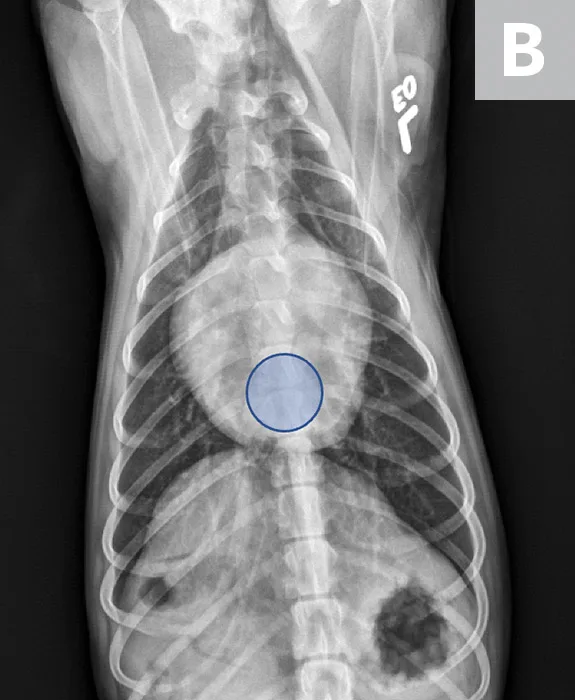

FIGURE 1

VLAS measurement in a dog with suspected stage B1 MMVD using a left lateral radiograph (A). A caliper was used to measure from the center of the most ventral aspect of the carina to the most caudal aspect of the left atrium, where it intersects with the dorsal border of the caudal vena cava. This measurement was transferred to the cranial aspect of T4 and extended caudally along the thoracic vertebrae. The number of vertebrae this line transversed was rounded to the nearest tenth to determine VLAS (2.1 VBUs). Stage B1 MMVD was confirmed via echocardiography. A redundant dorsal tracheal membrane, gastric food/foreign material, and mild T3 to T4 spondylosis deformans can also be seen. An orthogonal radiograph of the patient provides a more complete evaluation of cardiac silhouette (B); normal location of the left atrium is indicated (circle).